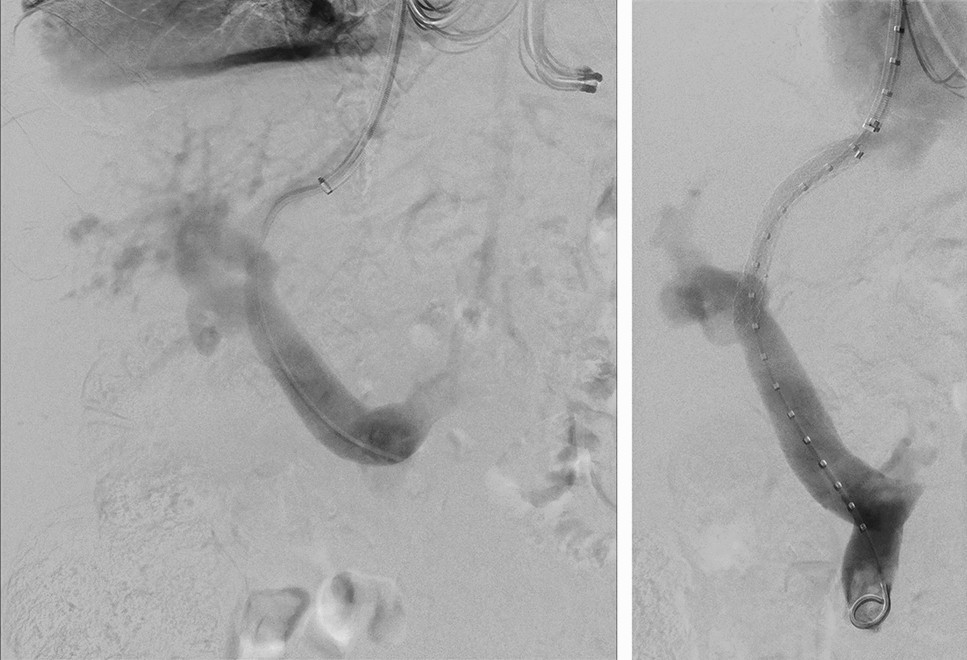

Figure 3

TIPS insertion. The initial TIPS in a 79-year-old male patient was placed from the middle hepatic vein to the left portal vein due to refractory ascites with esophageal varices (Gore Viatorr stent; 8 mm diameter; 60 × 20 mm).